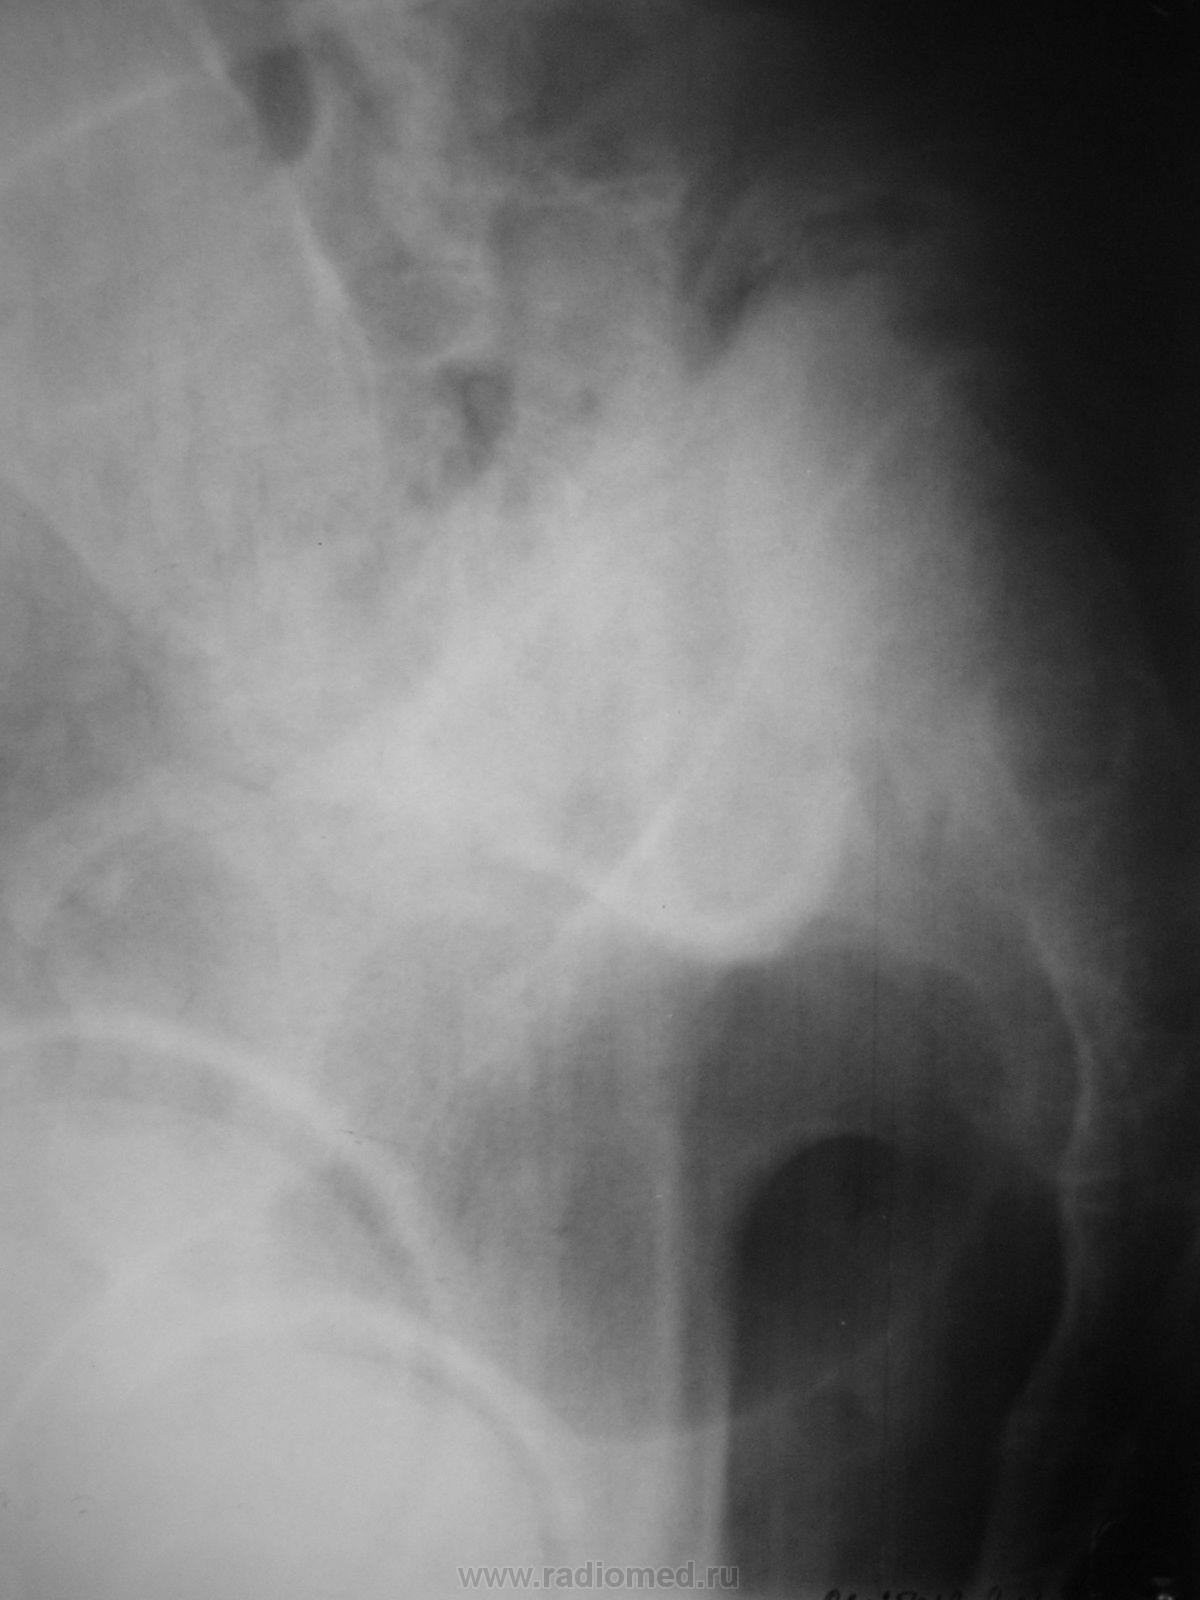

Пол пациента: Мужской пол Тип патологии: Другое Область исследования: Скелетно-мышечная система Методы исследования: Rg К сожалению опять могу представить только один снимок, думаю такое встречается не часто. Больной страдает много лет, но оперироваться не решается... ID:601 Вс, 24/01/2010 - 13:24 #1 Катенёв Валенти... Не на сайте Был на сайте: 6 лет 11 месяцев назад Зарегистрирован: 22.03.2008 - 22:15 Публикации: 54876 До конца не пойму. Вижу, что "что-то" поехало, по всей видимиости, часть крестца во всем позвоночным столбом кпереди и книзу. Интересно-было-бы глянуть прямой снимок, глянуть к чему "приколочены" подвздошные кости. Вс, 24/01/2010 - 14:13 #2 Анатолий Владим... Не на сайте Был на сайте: 7 лет 9 месяцев назад Зарегистрирован: 16.10.2009 - 21:16 Публикации: 1941 А остальное - сьехало...

До конца не пойму. Вижу, что "что-то" поехало, по всей видимиости, часть крестца во всем позвоночным столбом кпереди и книзу. Интересно-было-бы глянуть прямой снимок, глянуть к чему "приколочены" подвздошные кости.

А остальное - сьехало...